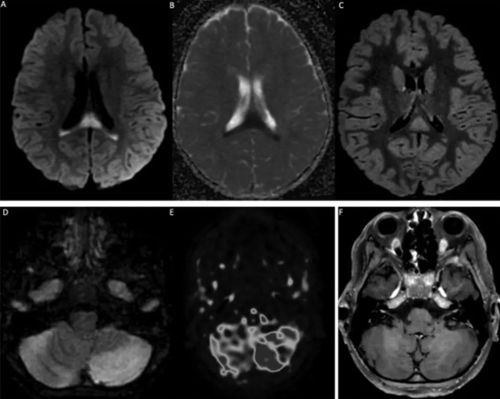

该研究显示,所有患者都有SARS-CoV-2暴露史或核酸检测阳性。在神经系统疾病发作时,8名儿童的新冠病毒核酸检测仍是呈阳性(鼻咽拭子)。58%的患儿(11人)脑脊液异常,74%的儿童(14人)出现MRI异常。

19名儿童中有11名出现多细胞增多症(中位数23白细胞/μL,最大300,以淋巴细胞或中性粒细胞为主)。单核细胞增生李斯特菌PCR、巨细胞病毒、肠道病毒、单纯疱疹病毒1和2、人疱疹病毒6、副胆囊病毒和水痘-带状疱疹病毒在所有儿童的脑脊液中均为阴性。19例患者中只有1例脑脊液常规检验出现蛋白升高,≥50mg/dL。在10名测试患者中的2名患者中鉴定出脑脊液寡克隆区带(判断鞘内免疫球蛋白合成的金标准)。在对9名患者进行测试时,脑脊液中的干扰素α分泌始终为阴性。在9名患者中测量了脑脊液中的细胞因子(IL1、IL6、IL10、TNF),其中3名患者异常:2名儿童中存在单一的IL6升高(1118和1551pg/ml,正常值200倍);一名儿童的所有3种细胞因子增加≤10倍正常值。

19名患者中有14名MRI异常。4例MRI显示ADEM伴有多灶性脑损伤,1例伴有视神经炎;3例显示胼胝体细胞毒性病变(CLOCC综合征),胼胝体压部扩散受限,T2-FLAIR高信号,2例小脑炎;1例分别显示孤立性视神经炎、孤立性面神经炎和多发性神经炎。19例脊柱MRI中有5例异常:5例显示脊髓炎,其中3例与ADEM相关,1例为孤立性,1例与马尾神经根的对比增强相关。所有脊髓炎病例均显示超过3个椎体受累。